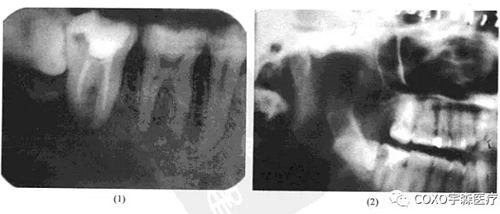

(二)牙骨質(zhì)骨化性纖維瘤

病例 女性,50歲,因[6區(qū)不適在某醫(yī)院攝片發(fā)現(xiàn)6根尖區(qū)有1.5cm×1.5cm陰影而來就診。檢查:[67已行單端固定橋修復,無明顯叩痛與松動。下頜全景片示:根尖陰影,周邊整齊,中央有一小游離骨塊狀物。牙片示陰影與[6根尖緊密接觸。疑為[6根尖周炎及局限性死骨形成(圖13-9),拆除[67單端固定橋,發(fā)現(xiàn)[6為活髓,行根管治療術后,手術探查,去除病變組織,病理最后診斷為牙骨質(zhì)骨化性纖維瘤。

分析與評述

牙骨質(zhì)骨化性纖維瘤(cemento-ossifying fibroma),病理上屬纖維-骨病變類型。以前,本病曾稱“化牙骨質(zhì)纖維瘤”(cementifying fibroma),并將其列為牙骨質(zhì)瘤的一個亞型。由于牙骨質(zhì)也是一種紡織狀骨,且在病理上與骨化性纖維瘤也很難鑒別,因此,從1992年以后修訂的WHO分類中,已將此兩類病變合稱,并被命名為牙骨質(zhì)骨化性纖維痛。

牙骨質(zhì)骨化纖維瘤臨床上多發(fā)生在牙根部位,不僅有骨小梁形成,而且有牙骨質(zhì)形成,因而將其歸類為牙源性腫瘤。在臨床上并不多見,但其早期僅呈現(xiàn)根尖部頜骨內(nèi)病損時,則易與根尖周病混淆。本病例病灶不大,位于根尖,牙片顯示陰影與[6關系十分密切,[6有冠修復,但未見行根管治療術,故疑為慢性根尖周炎;由于其中有一小團密度與骨質(zhì)相似的鈣化影,故又疑是否為炎癥導致的死骨殘留。然而拆除[67單端固定橋后,發(fā)現(xiàn) 為活髓,就此否定了根尖周炎的診斷。最后經(jīng)手術證實為牙骨質(zhì)骨化性纖維瘤。本例的診治經(jīng)驗提示:牙骨質(zhì)骨化性纖維瘤早期的 線片可呈不典型表現(xiàn)

(此患者的 線片表現(xiàn)與骨化性骨纖維瘤的多囊、骨質(zhì)鈣化、疏松不一等基本表現(xiàn)完全不一致);為排除根尖周病,牙髓是否有活力存在,也是關鍵的鑒別點